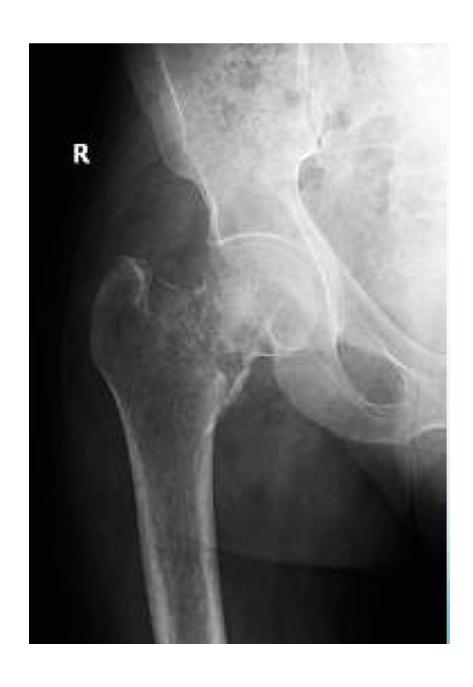

A 50-year-old male tripped over the edge of carpet at home. He heard a crack and is unable to walk. He gave history of progressive weight loss. On clinical examination, he was in pain with a deformity at upper right thigh. He looks pale.

What are the key x-ray findings?

- Decreased bone density in the right proximal femur

- Fracture in the neck of the femur

- AP view of the right proximal femur

What is the diagnosis?

- Pathological fracture due to osteoporosis